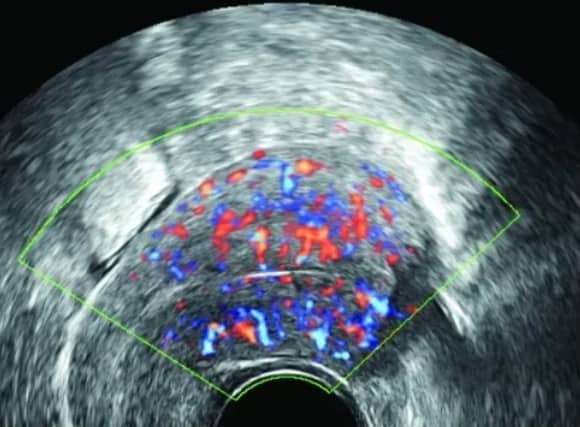

宫腔粘连自查与检查方法

如果你有这些情况,可能需要警惕宫腔粘连,早点发现早点治疗,效果会好一些。 自查的迹象 月经一直很规律,但人流或产后断奶后40天还没来月经,最好去医院看看......